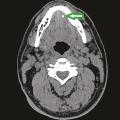

Pathologies lithiasiques des glandes salivaires

Parmi les pathologies des glandes salivaires, les lithiases des canaux salivaires sont les plus fréquentes, avec une incidence entre 1 pour 10 000 et 1 pour 20 000.1 Elles représentent environ 60 % des cas d’obstruction des canaux salivaires et s’observent à tout âge. Les lithiases sont plus fréquemment retrouvées dans les…